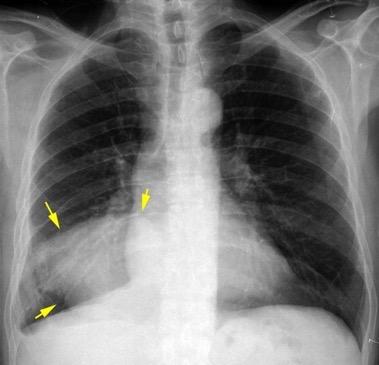

Consolidación por Infarto pulmonar. (TEP)

Tromboembolismo pulmonar Diafragma elevado 20%